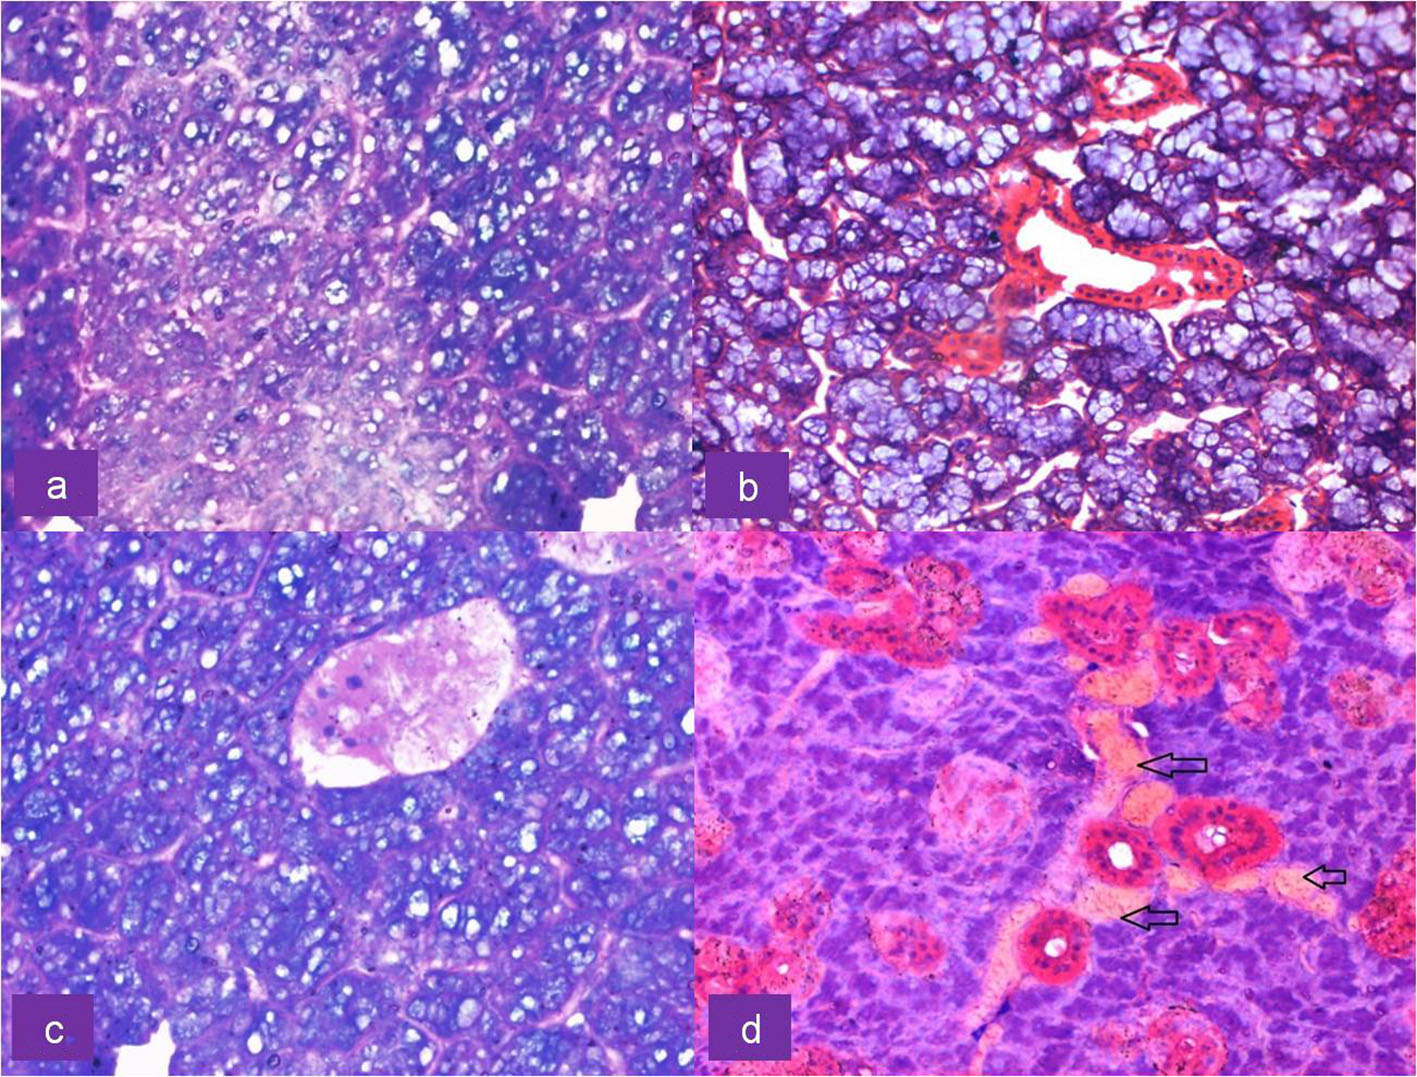

Representative images of histomorphometric analysis of normal and irradiated glands by Image J software are shown in Figure 1. Under light microscopy, H&E sections of control submandibular glands showed characteristic secretory acinar histology. They were mainly of the serous type and were composed of pyramidal cells surrounding a narrow lumen with foamy basophilic cytoplasm and a rounded basal nucleus. Duct system consisted of intercalated ducts and granular convoluted tubules (GCTs) with columnar cells containing excretory granules and ducts. Normal neurovascular bundle was seen close to the excretory ducts. Irradiated submandibular glands exhibited acinar atrophy and shrinkage with varying degrees of ductal (GCT) degeneration (Fig. 2). Secretory acinar cells also showed generalized cytoplasmic vacuolation and increased acinar widening, though mucous acinar cells retained their shape and morphology (Fig. 3). Details of morphometric analysis are shown in Table 1.

![]() Click for large image | Figure 3. Upper row: H&E-stained section of irradiated submandibular gland showing (a) cytoplasmic vacuolation of serous acini at × 40 magnification and (b) mucous acini exhibiting no morphological alterations at × 20 magnification. Lower row: H&E-stained section of irradiated serous acini showing (c) pyknotic nuclei and nuclear fragmentation along with vacuolation at × 40 magnification and (d) congestion of blood vessels (arrows) at × 20 magnification. |

Serous acinar area was calculated as overall percentage of acinar cell compartment in the H&E photomicrograph. Acinar area was reduced from 77% to 36% with shape change: rounded to angulated and shrunken morphology. The mean serous acinar cell size displayed a significant (P < 0.001) shrinkage from 3,447.53 ± 461.03 to 428.25 ± 75.22 mm2. Numerous vacuoles were seen which occupied an average area of 56.18 ± 18.62 mm2 in randomly selected areas of each sample. There was a significant increase in the inter-acinar space compared to the controls: 10.08 ± 0.60 vs. 3.46 ± 0.67 mm. Ductal cells showed degeneration at places with few nuclear changes. Fragmentation was present. Endothelial cells and neural tissue did not exhibit much change except for the congestion of blood vessels (Fig. 3). Nuclei of irradiated gland acini exhibited varied size (anisonucleosis) and shape (poikilonucleosis) with irreversible condensation of the chromatin (pyknotic) nuclei. However, nuclei of the irradiated gland ducts were not affected. No significant difference was noticed in the ductal nuclear size. No adipose tissue was noticed in any of the irradiated samples. The comparison of histomorphometric parameters is given in Table 2. Box plots describing the mean values and the interquartile range are shown in Figure 4.